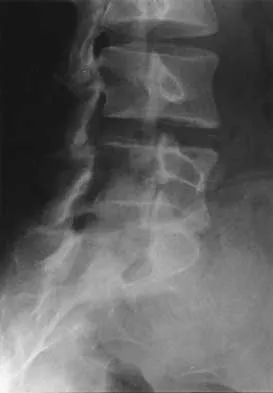

A 19-year-old woman reports lower back pain following a motor vehicle accident. Radiographs obtained immediately after the accident and a bone scan obtained 4 weeks later are shown in Figures 25a through 25c. The patient asks questions regarding the cause, genetics, and natural history of her condition. She should be informed that the condition was

The radiographs show L5 spondylolysis without spondylolisthesis (slip). The bone scan is normal, indicating that the pars interarticularis fractures are not acute. The incidence of spondylolysis is approximately 5% in the general population. The lesion generally develops in children age 5 to 6 years, and there is a second peak in the adolescent population. There is a familial predisposition, with reported rates of 27% to 69% in close relatives. A recent long-term follow-up study found that 90% of the spondylolisthesis had occurred before the patient's first visit to the physician. Spondylolisthesis tends to progress during the initial growth spurt and is similar in some respects to idiopathic scoliosis. Progression of a lytic spondylolysis to spondylolisthesis in adulthood has been reported; however, this is exceedingly rare. Lauerman WC, Cain JE: Isthmic spondylolisthesis in the adult. J Am Acad Orthop Surg 1996;4:201-208. Hensinger RN: Spondylolysis and spondylolisthesis in children and adolescents. J Bone Joint Surg Am 1989;71:1098-1107. Seitsalo S, Osterman K, Hyvarinen H, Tallroth K, Schlenzka D, Poussa M: Progression of spondylolisthesis in children and adolescents: A long-term follow-up of 272 patients. Spine 1991;16:417-421.